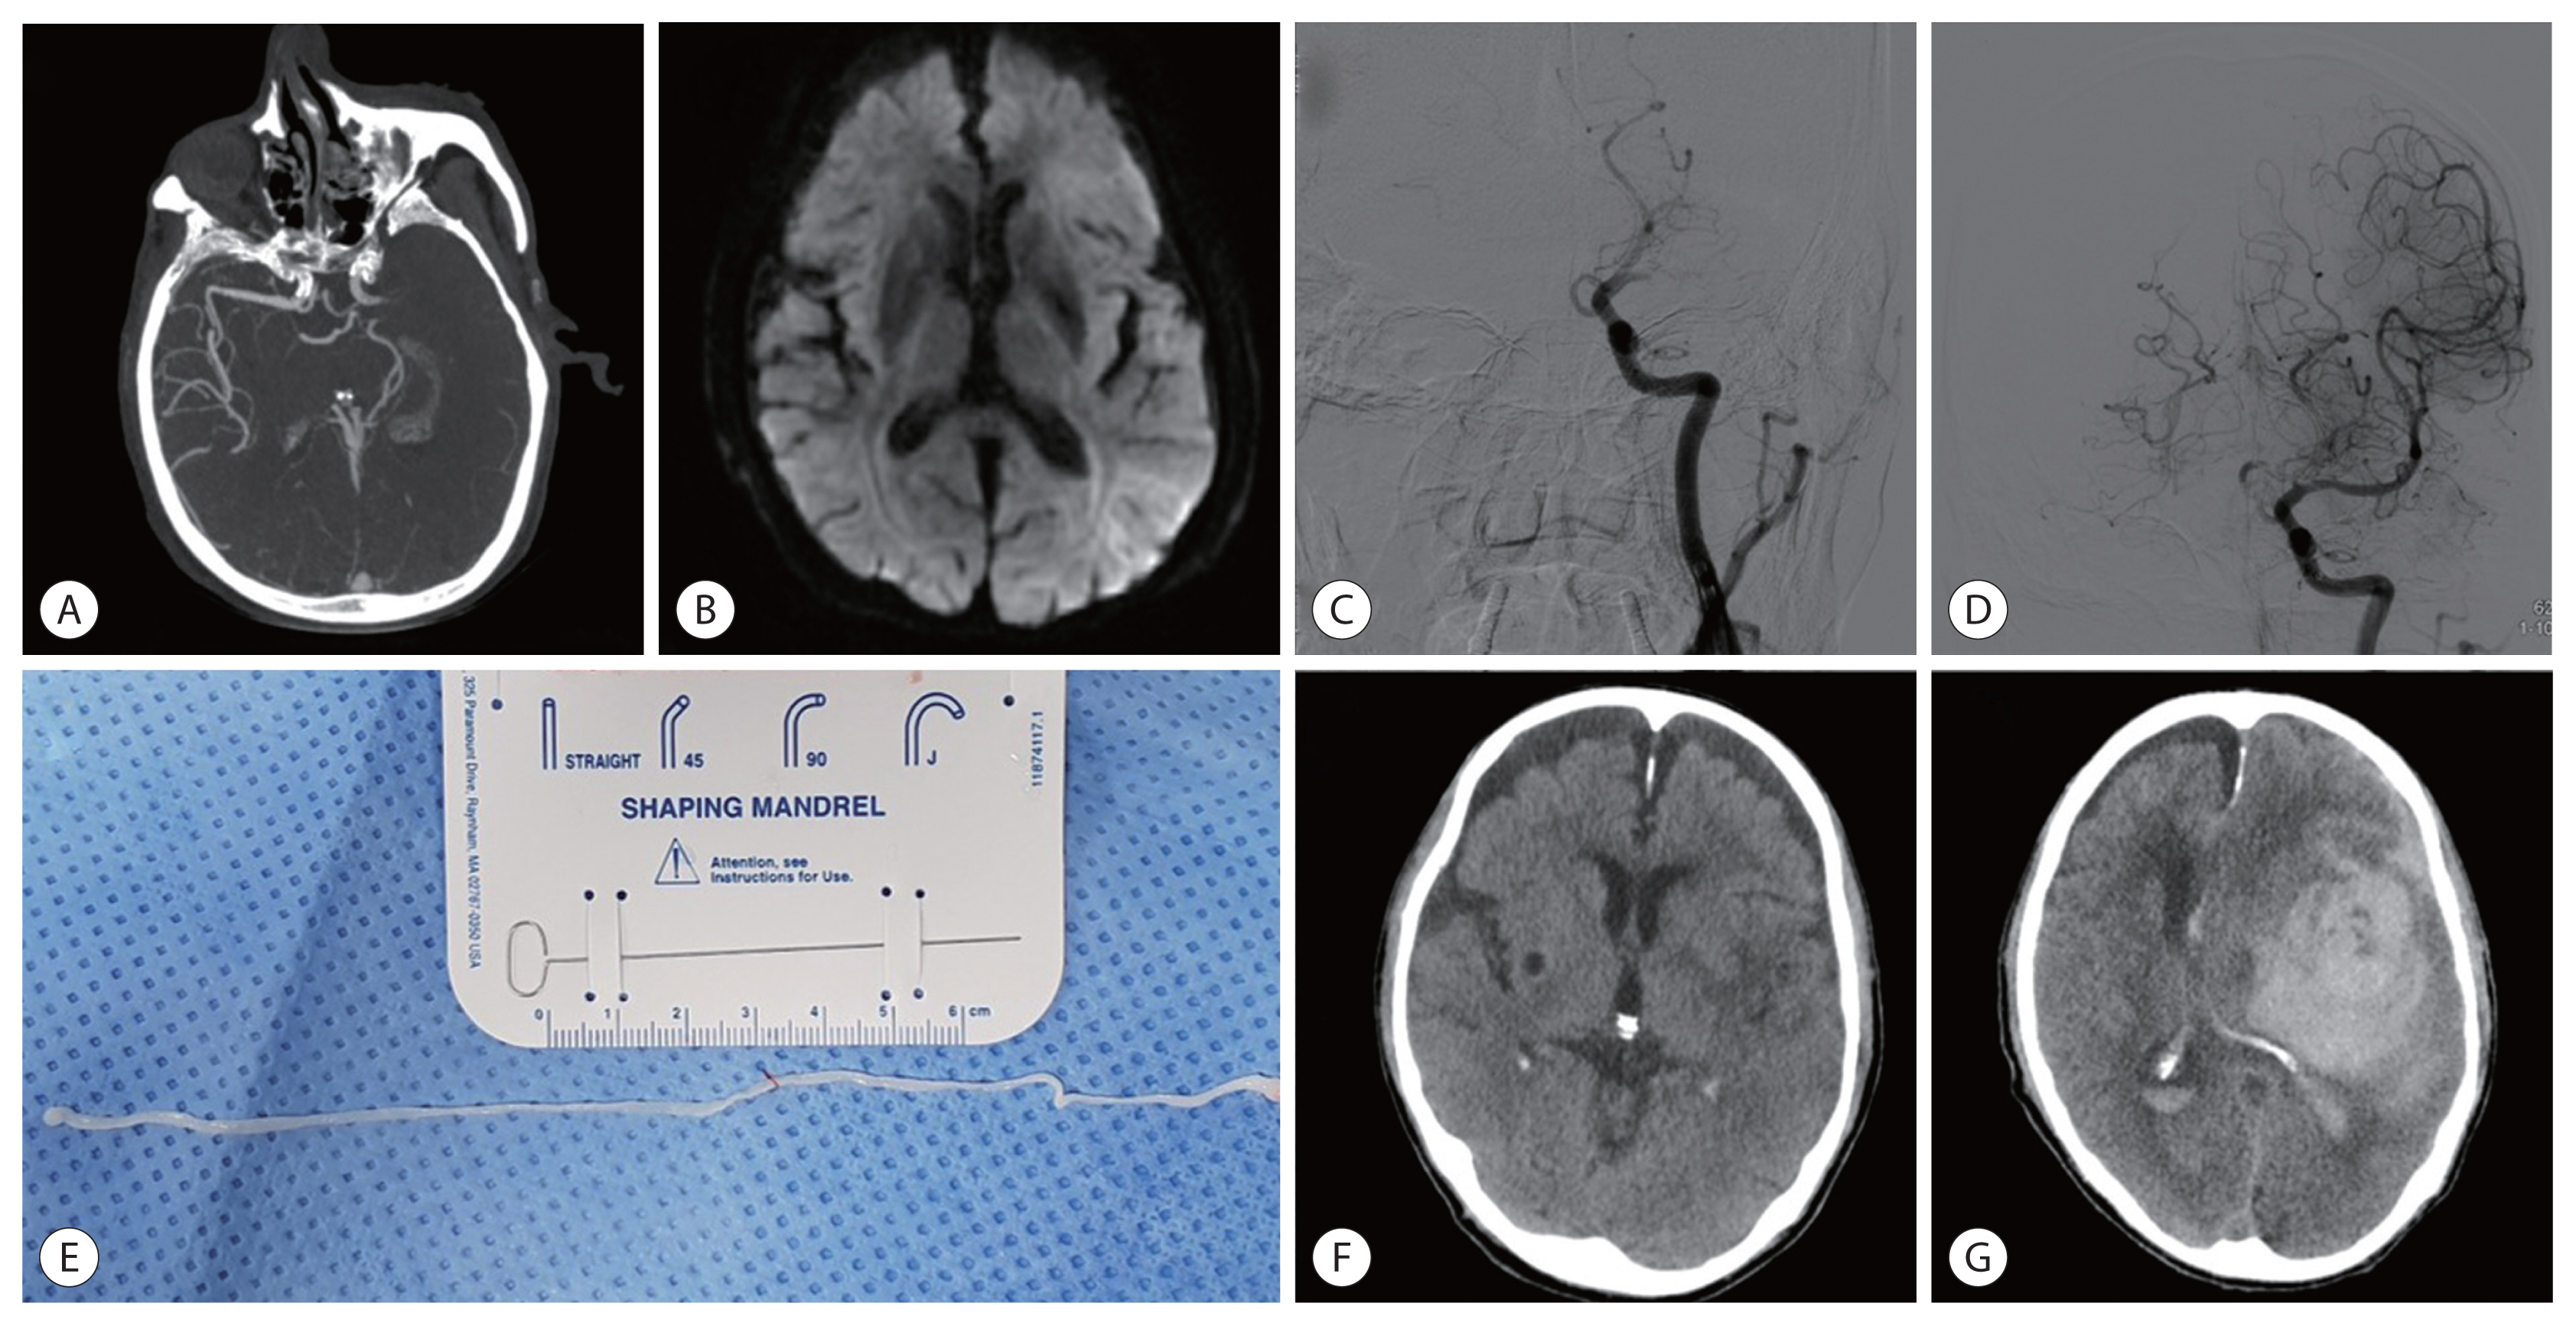

A Retrieved Sparganum of Spirometra erinaceieuropaei from a Korean Man during Mechanical Thrombectomy